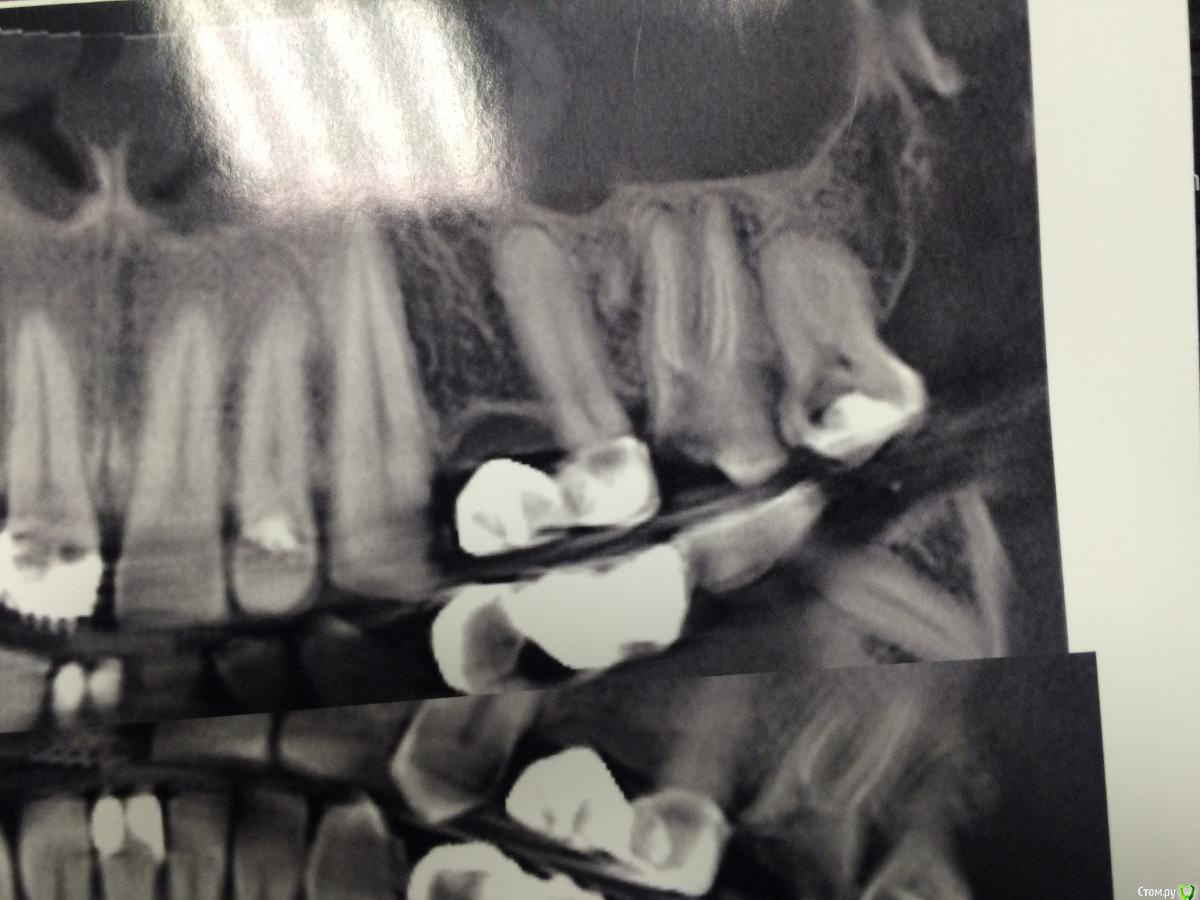

Shargik Опубликовано 23 октября, 2015 Поделиться Опубликовано 23 октября, 2015 Господа эндодонтисты, вот Вам такой случай.. Как думаете, стоит с ним повоевать, или сразу в плевашку? Беспокоит выбухание на небе и свищ с непрекращающимся гноетечением, каналы все проходимы, вот думаю, что с ним делать. Кто прилагается.. Ссылка на комментарий

Shargik Опубликовано 23 октября, 2015 Автор Поделиться Опубликовано 23 октября, 2015 Зуб 26, на небном корне обширный процесс. С небной стороны кости нет от слова совсем. В том то и дело, что пациент не сильно платёжеспособен, думается мне попробовать полечить, авось косточки хоть чуть вырастет, или думаете, это с мельницами бодаться.. Ссылка на комментарий

Гарриевич Опубликовано 23 октября, 2015 Поделиться Опубликовано 23 октября, 2015 Я бы попробовал с зубом поработать учитывая хорошую проходимость каналов и сохранность твердях тканей. Остальные зубы в этой области витальны? Ссылка на комментарий

Shargik Опубликовано 23 октября, 2015 Автор Поделиться Опубликовано 23 октября, 2015 Я бы попробовал с зубом поработать учитывая хорошую проходимость каналов и сохранность твердях тканей. Остальные зубы в этой области витальны?ССпасибо большое, я и попробую, терять то нечего. 7-ка пока витальна, но там пульпит, пятерка живая, под штамповкой. Если экссудацию остановлю, то, думаю, все получится.. Ссылка на комментарий